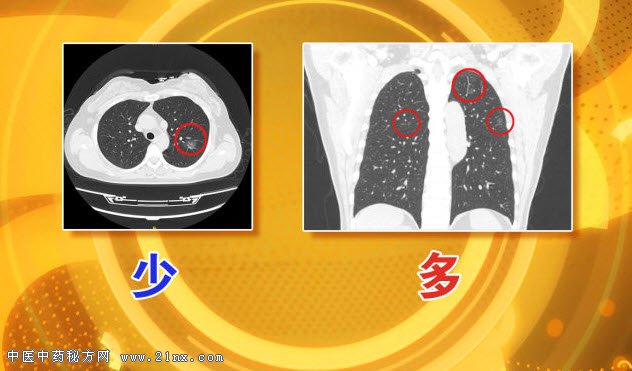

图:肺部结节多与少